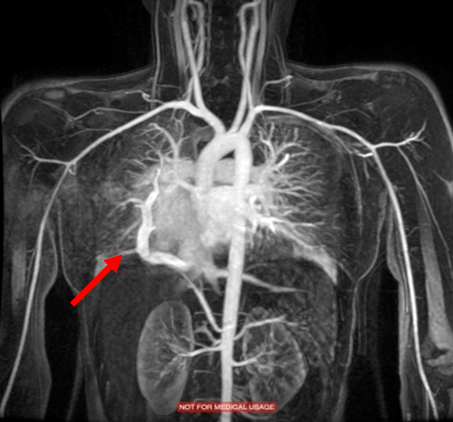

Routine laboratory analysis, including a complete blood count and metabolic panel, is normal. A postero-anterior chest roentgenogram is shown in Figure 1. Chest computed tomography (CT) without IV contrast (Figure 2), and gadolinium enhanced magnetic resonance angiogram (Figures 3 and 4) are also obtained. A decision is made to perform a cardiac catheterization (Figures 5 and 6) for further evaluation.

Figure 3

The red arrow (Figures 7, 8, 9, and 11) shows a large scimitar vein. Chest CT (Figure 8) shows partial anomalous pulmonary venous return from the right lower pulmonary vein into the inferior vena cava (IVC) and right-sided pulmonary hypoplasia with consequent dextro-position of the heart into the right hemithorax. The gadolinium-enhanced angiography cardiac magnetic resonance imaging (MRI) (Figure 9) with three-dimensional reconstruction (Figure 10, Video 1) confirms the diagnosis, which shows aortopulmonary collaterals from the descending abdominal aorta to the right lower lung lobe (one dot), large anomalous pulmonary vein, the scimitar vein (two dots), draining the right lower lung to the IVC (three dots). The right heart is within normal limits for size.